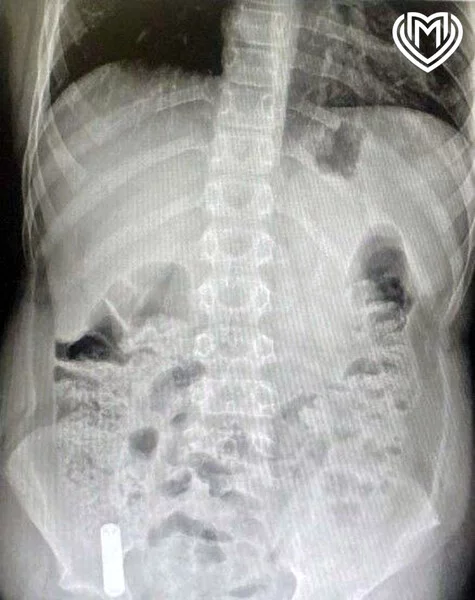

Moskvada G.N. Speranski adına Uşaq Xəstəxanasının həkimləri təsadüfən televizorun pultundakı barmaq tipli batareyanı udan 12 yaşlı oğlan uşağını xilas ediblər.

Valideynləri uşağı dərhal xəstəxanaya gətiriblər və onun televizor pultundakı batareyanı udduğunu bildiriblər. Yad cisim kor bağırsağa qədər düşüb.

Həkimin sözlərinə görə, batareya hələ oksidləşməyə başlamayıb, bu səbəbdən kimyəvi yanıq baş verməyib. Uşaq iki gün sonra tamamilə sağlam şəkildə evə buraxılıb.